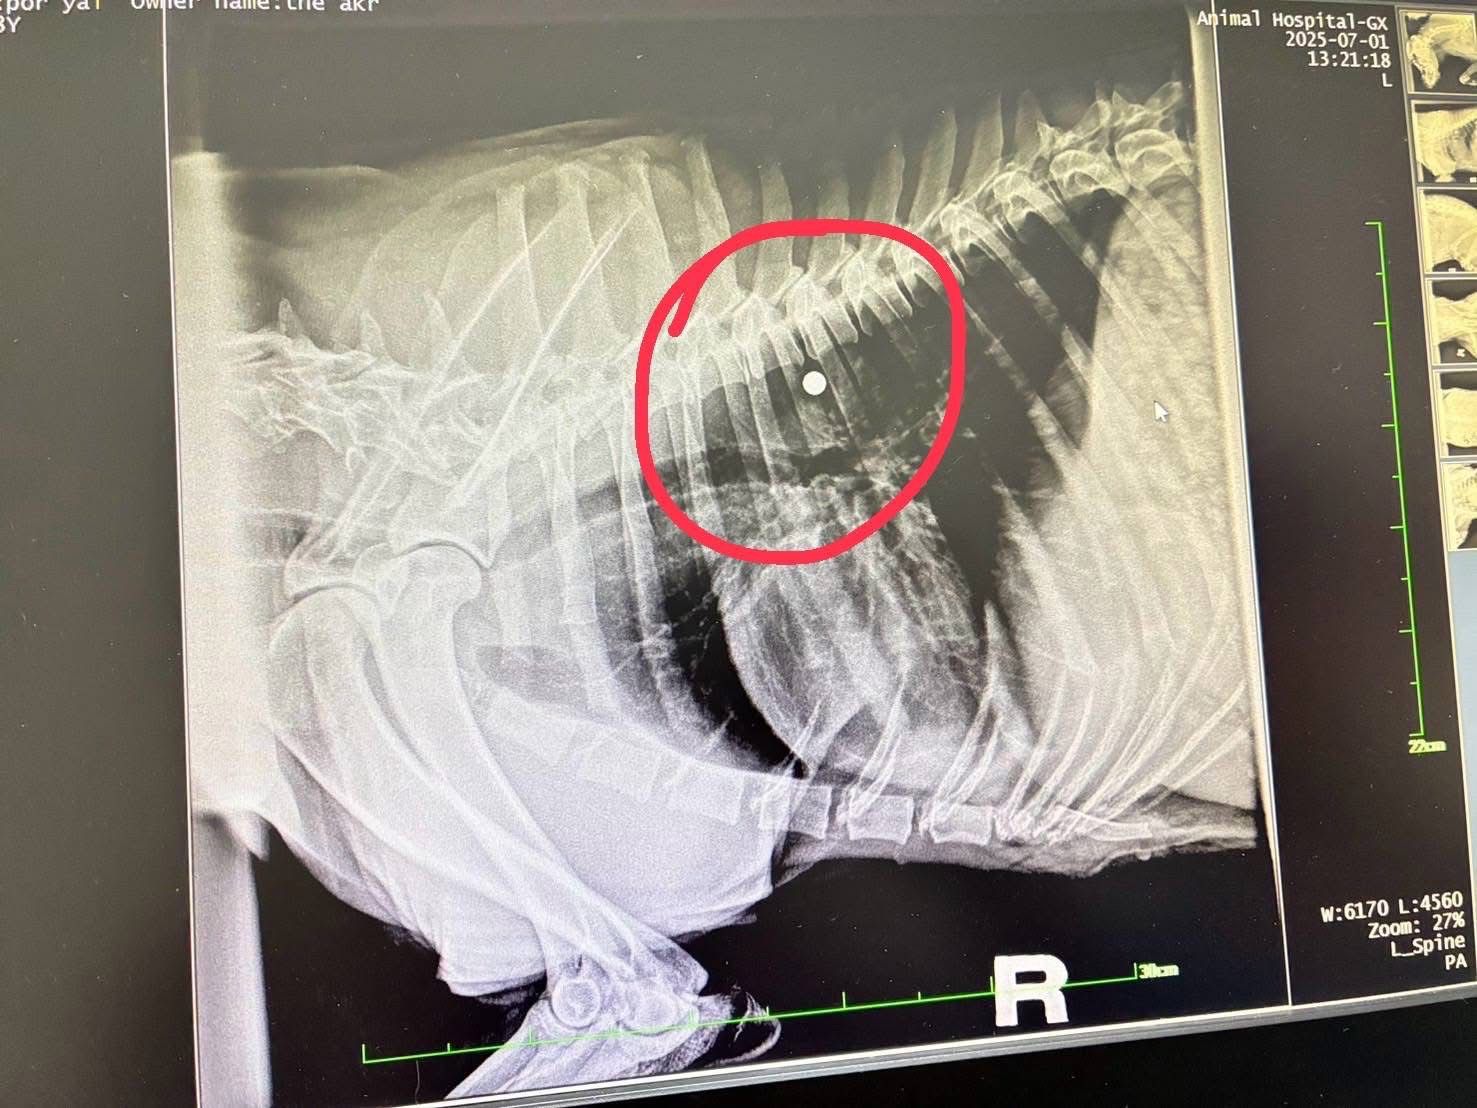

เมื่อวันที่ 1 กรกฎาคม 2568 พระครูสังฆรักษ์วีรวัฒน์ วีรวฑฺฒโน (พระครูอ๊อด) วัดเจดีย์หลวงวรวิหาร จังหวัดเชียงใหม่ เปิดเผยว่า ได้รับรายงานจากมูลนิธิ ดิอาร์ค ในพระราชูปถัมภ์ ซึ่งรับดูแลสุนัขพันธุ์ร็อตไวเลอร์จำนวน 4 ตัวที่ถูกนำไปทิ้งไว้กลางป่าในสภาพหิวโซและมีอาการบาดเจ็บหลายแห่ง โดยหนึ่งในสี่ตัวนั้นอยู่ในอาการบาดเจ็บสาหัส ล่าสุดเจ้าหน้าที่เไดมูลนิธิฯได้ทำการตรวจพบโลหะคล้ายกระสุนฝังอยู่ในร่างกายและอยู่ระหว่างดำเนินการผ่าตัดนำออกอย่างเร่งด่วน